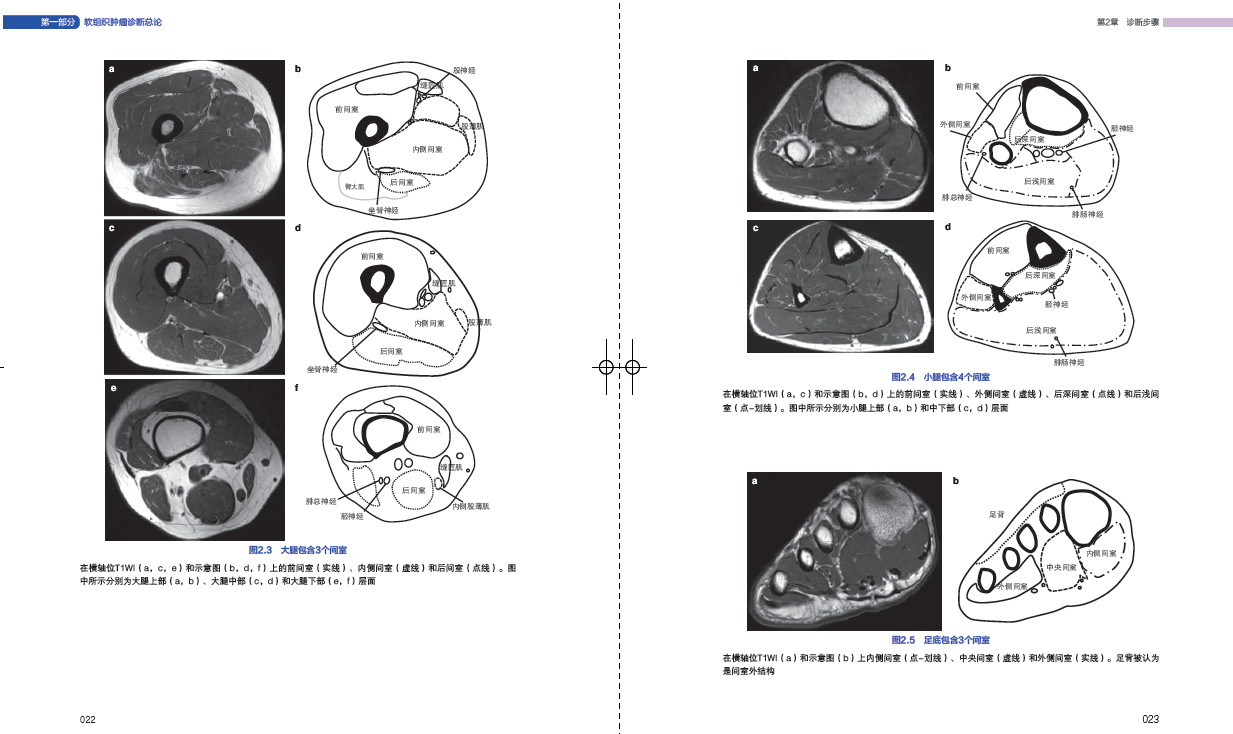

21 解剖间室018

23 示例:诊断步骤021